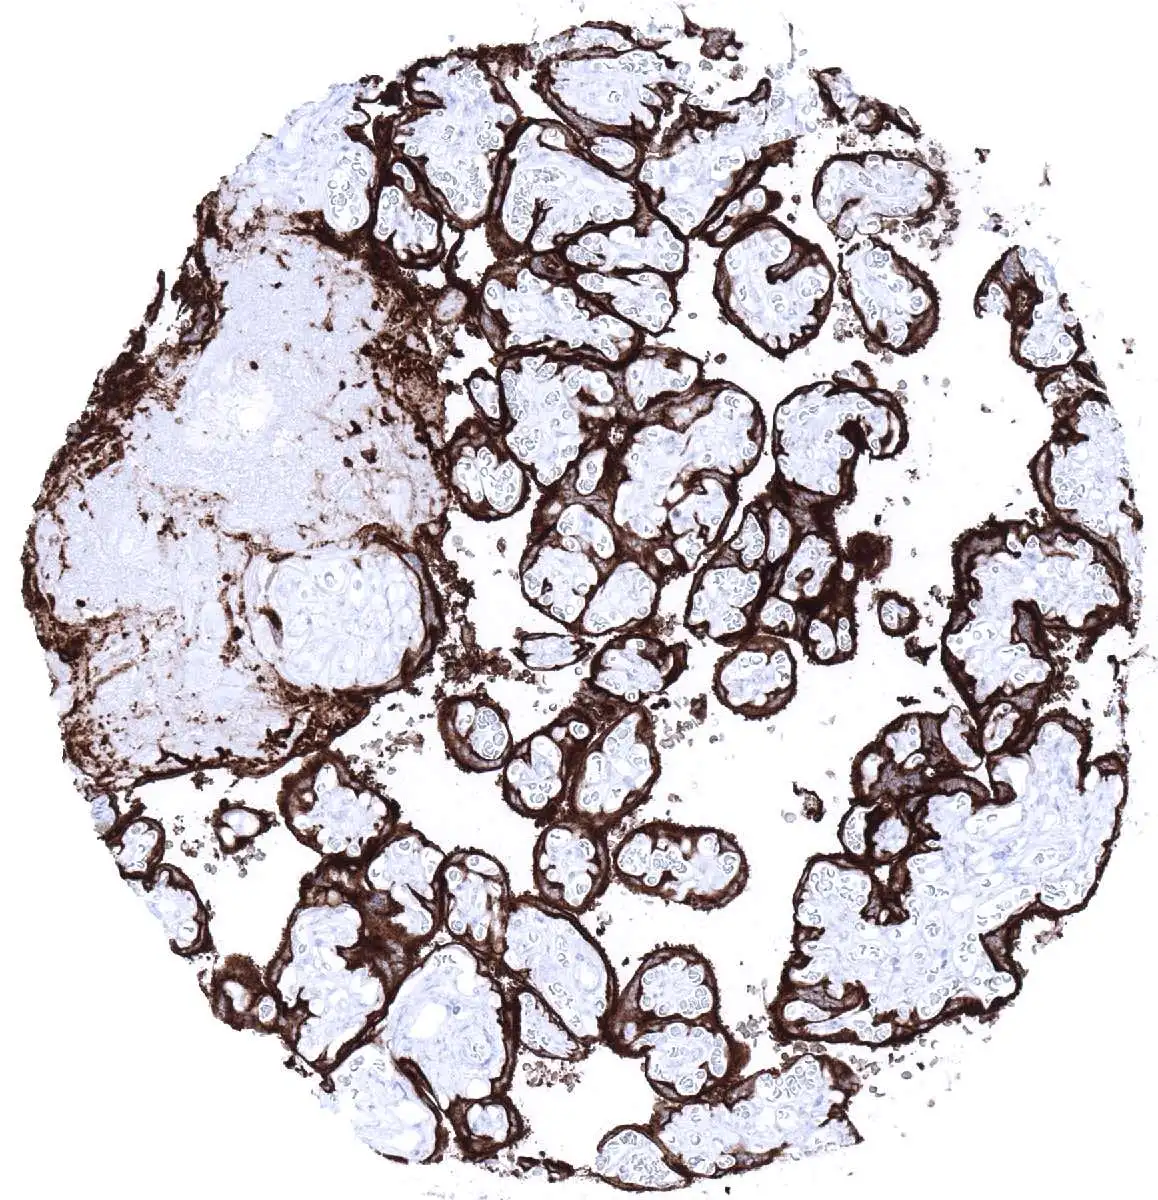

GTX04413 IHC-P Image

IHC-P analysis of human testicular seminoma tissue using GTX04413 Placental Alkaline Phosphatase antibody [MSVA-350R] HistoMAX™.

Strong Placental Alkaline Phosphatase Immunostaining in all cells of a testicular seminoma.